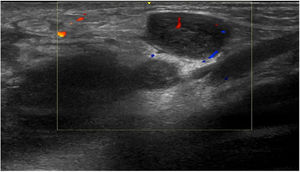

Three weeks later, the patient presented with an increase in size of the nodule in the left groin; the nodule then measured 8 cm, with a discrete fluctuation, and ultrasound was performed, together with fine-needle aspiration of the content of the lesion for a microbiological study. Ultrasound of the left groin showed multiple nodular images with hypervascularization, compatible with enlarged lymph nodes of significant size and appearance (Fig. 2). PCR of the aspirate was positive for serovar L C. trachomatis.